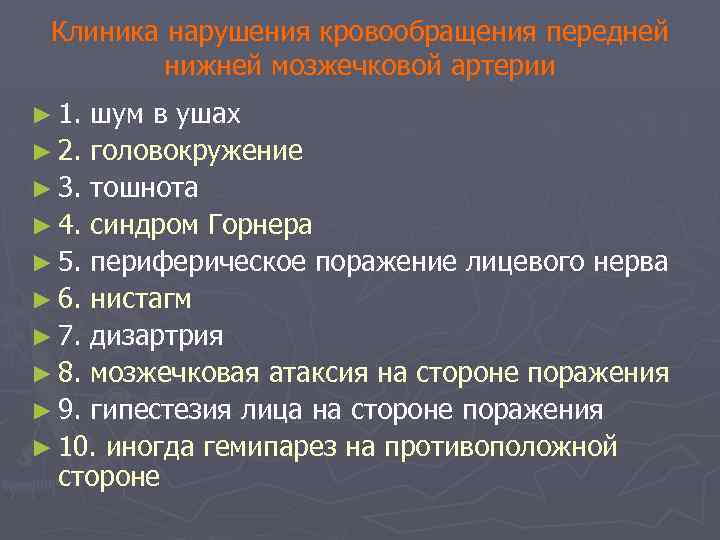

Клиника нарушения кровообращения передней нижней мозжечковой артерии ► 1. шум в ушах ► 2. головокружение ► 3. тошнота ► 4. синдром Горнера ► 5. периферическое поражение лицевого нерва ► 6. нистагм ► 7. дизартрия ► 8. мозжечковая атаксия на стороне поражения ► 9. гипестезия лица на стороне поражения ► 10. иногда гемипарез на противоположной стороне